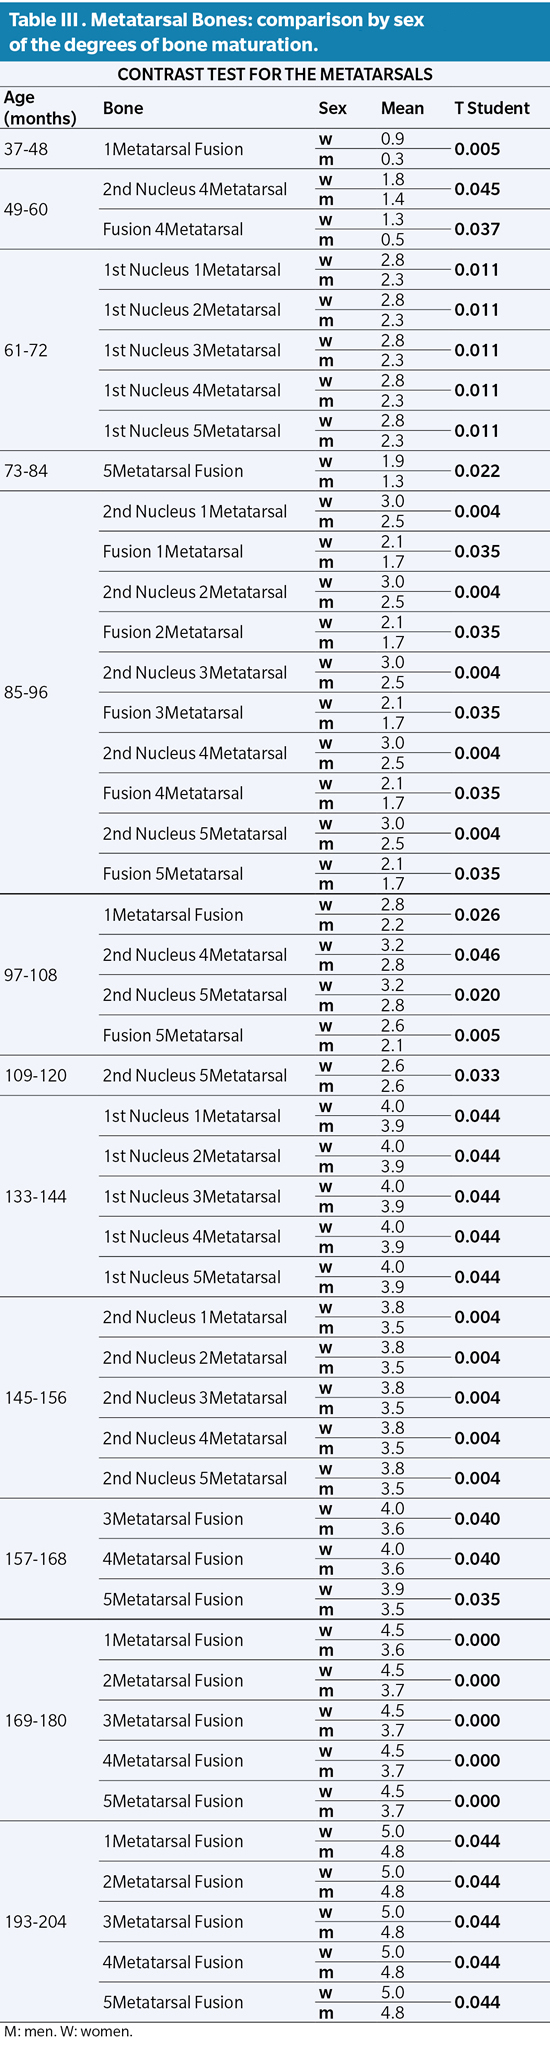

Similarly, the study of the metatarsals shows a delay in ossification of boys with respect to girls. All the ossification nuclei of the Metatarsus are significant, however, it should be noted that the first ossification nucleus of the Metatarsals has a difference by sex greater than 5 to 6 years (61 to 72 months with P value ≤0.011). The same occurs with the ossification of the second metatarsal ossicle between 7 and 8 years (85 to 96 months with P value ≤0.004). The fusions between primary and secondary nuclei have their greatest statistical significance around the mean age interval of 14 to 15 years (169-180 months with P value ≤0.000), where the delay in the rate of ossification in sex becomes more evident. male versus female (Table III).

The values obtained after our analysis in the metatarsals do not differ much from the ages established in the scientific literature, however, it is worth noting the simultaneous maturational behavior among the five metatarsals, which differs with some authors who affirm that the first metatarsal ossifies. regardless of the rest22. Something similar occurs with the study of fingers. Some authors affirm the difference in the maturational rhythm between the Phalanges of the different fingers, as well as between themselves4,18 a matter in which we disagree, since our results show, in general lines, a uniform maturational rhythm in the entirety of the fingers and between Phalanges23.

Our results coincide with what is established in the classical literature regarding the differentiation of bone maturation by sex, confirming that epiphyseal fusions occur earlier in females than in males. In addition, we affirm that this situation occurs not only in bone fusions but also in the appearance of most of the nuclei, both primary and secondary, according to what was established by Seucher4.

Nor is the rate of maturation the same for both sexes. This issue was already mentioned by Robledo without specifying exactly which of the two sexes evolved faster or slower. Based on our results, we are able to affirm that the rate of maturation is slower in boys than in girls6.